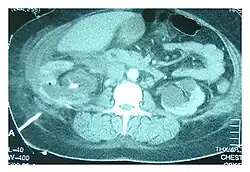

CT scan showing nephrostomy tube, indicated by the white line on the bottom left, in a case of urinothorax being treated

Abdominal ultrasonography and CT scan can help diagnose the underlying condition of the genitourinary tract. If other methods prove inconclusive, an accurate diagnosis can be made by a technetium-99m kidney scan, which shows albumin labeled with 99Tc that translocates into the pleural space from the genitourinary tract.[4]